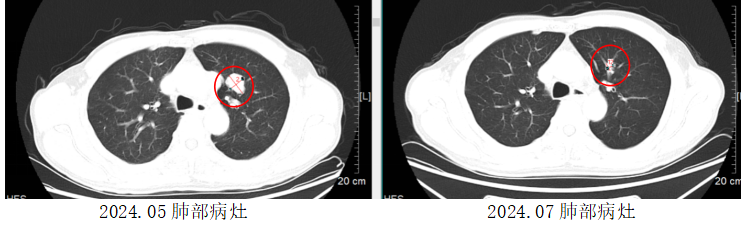

胡先生起初对参与临床研究顾虑重重,担心临床研究中采用的新药可能带来的风险。但经过悉心解释说明和沟通,逐渐打消了他的疑虑。在接受1个周期治疗后,他原来颈部及腋窝肿大的淋巴结就触诊不到了。2个周期治疗后复查CT,全身转移的肿瘤病灶明显退缩,相比最初缩小了一半以上。目前,胡先生已接受5个周期的治疗,肿瘤仍在进一步退缩中。